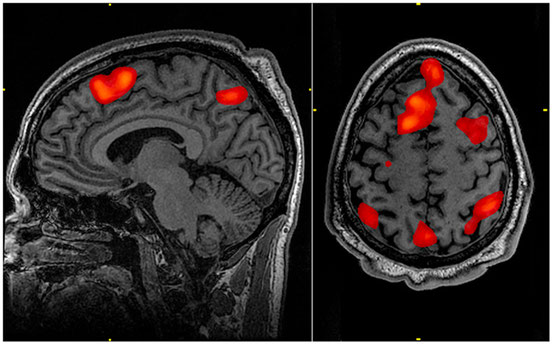

Diese materielle Grundlage von Willensentscheidungen ist laut Neurowissenschaften ein multizentrisches Entscheidungsnetzwerk in vier Teilen des Gehirns, welche die Persönlichkeit des Individuums konstituieren, aufgrund dessen entschieden wird:

Diese Vorgänge und Zustände werden nicht bewusst erlebt, wurden bezüglich ihrer großen Bedeutung für die Entscheidungsbildung des Individuums allerdings in den letzten Jahren durch psychologische und neurobiologische Untersuchungen belegt[6]. So findet bevor (!) uns ein Gedanke, eine Vorstellung oder ein Wunsch bewusst wird, eine komplexe Aktivität im limbischen System, im Thalamus und in der Großhirnrinde statt[7], was den Fehlschluss nahelegt, Gedanken, Vorstellungen oder Wünsche kämen „aus dem Nichts“.